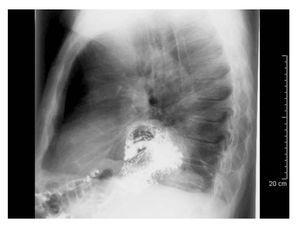

Hombre de 75 años con historia de dolor abdominal inespecífico crónico que ingresó a urgencias con un cuadro de pocas horas de evolución caracterizado por dolor torácico y epigástrico intenso, irradiado hacia la espalda y asociado a náusea sin vómito. Al examen físico se encontró dolor abdominal en epigastrio sin datos de alarma. Los estudios de sangre fueron normales. En la radiografía de tórax se encontró una imagen de nivel hidroaéreo en el hemitórax izquierdo. El protocolo de estudio se completó mediante una endoscopia y serie esófago-gastroduodenal en la cual se confirmó el diagnóstico de vólvulo gástrico órgano-axial (Figuras 2 y 3). El paciente fue llevado a la sala de operaciones para la realización de devolvulación y reducción gástrica hacia el abdomen, plastía diafragmática y funduplicatura tipo Toupet por laparoscopia.

¿ Figura 3. Serie gastroduodenal proyección lateral que muestra la torsión gástrica en sentido anteroposterior.